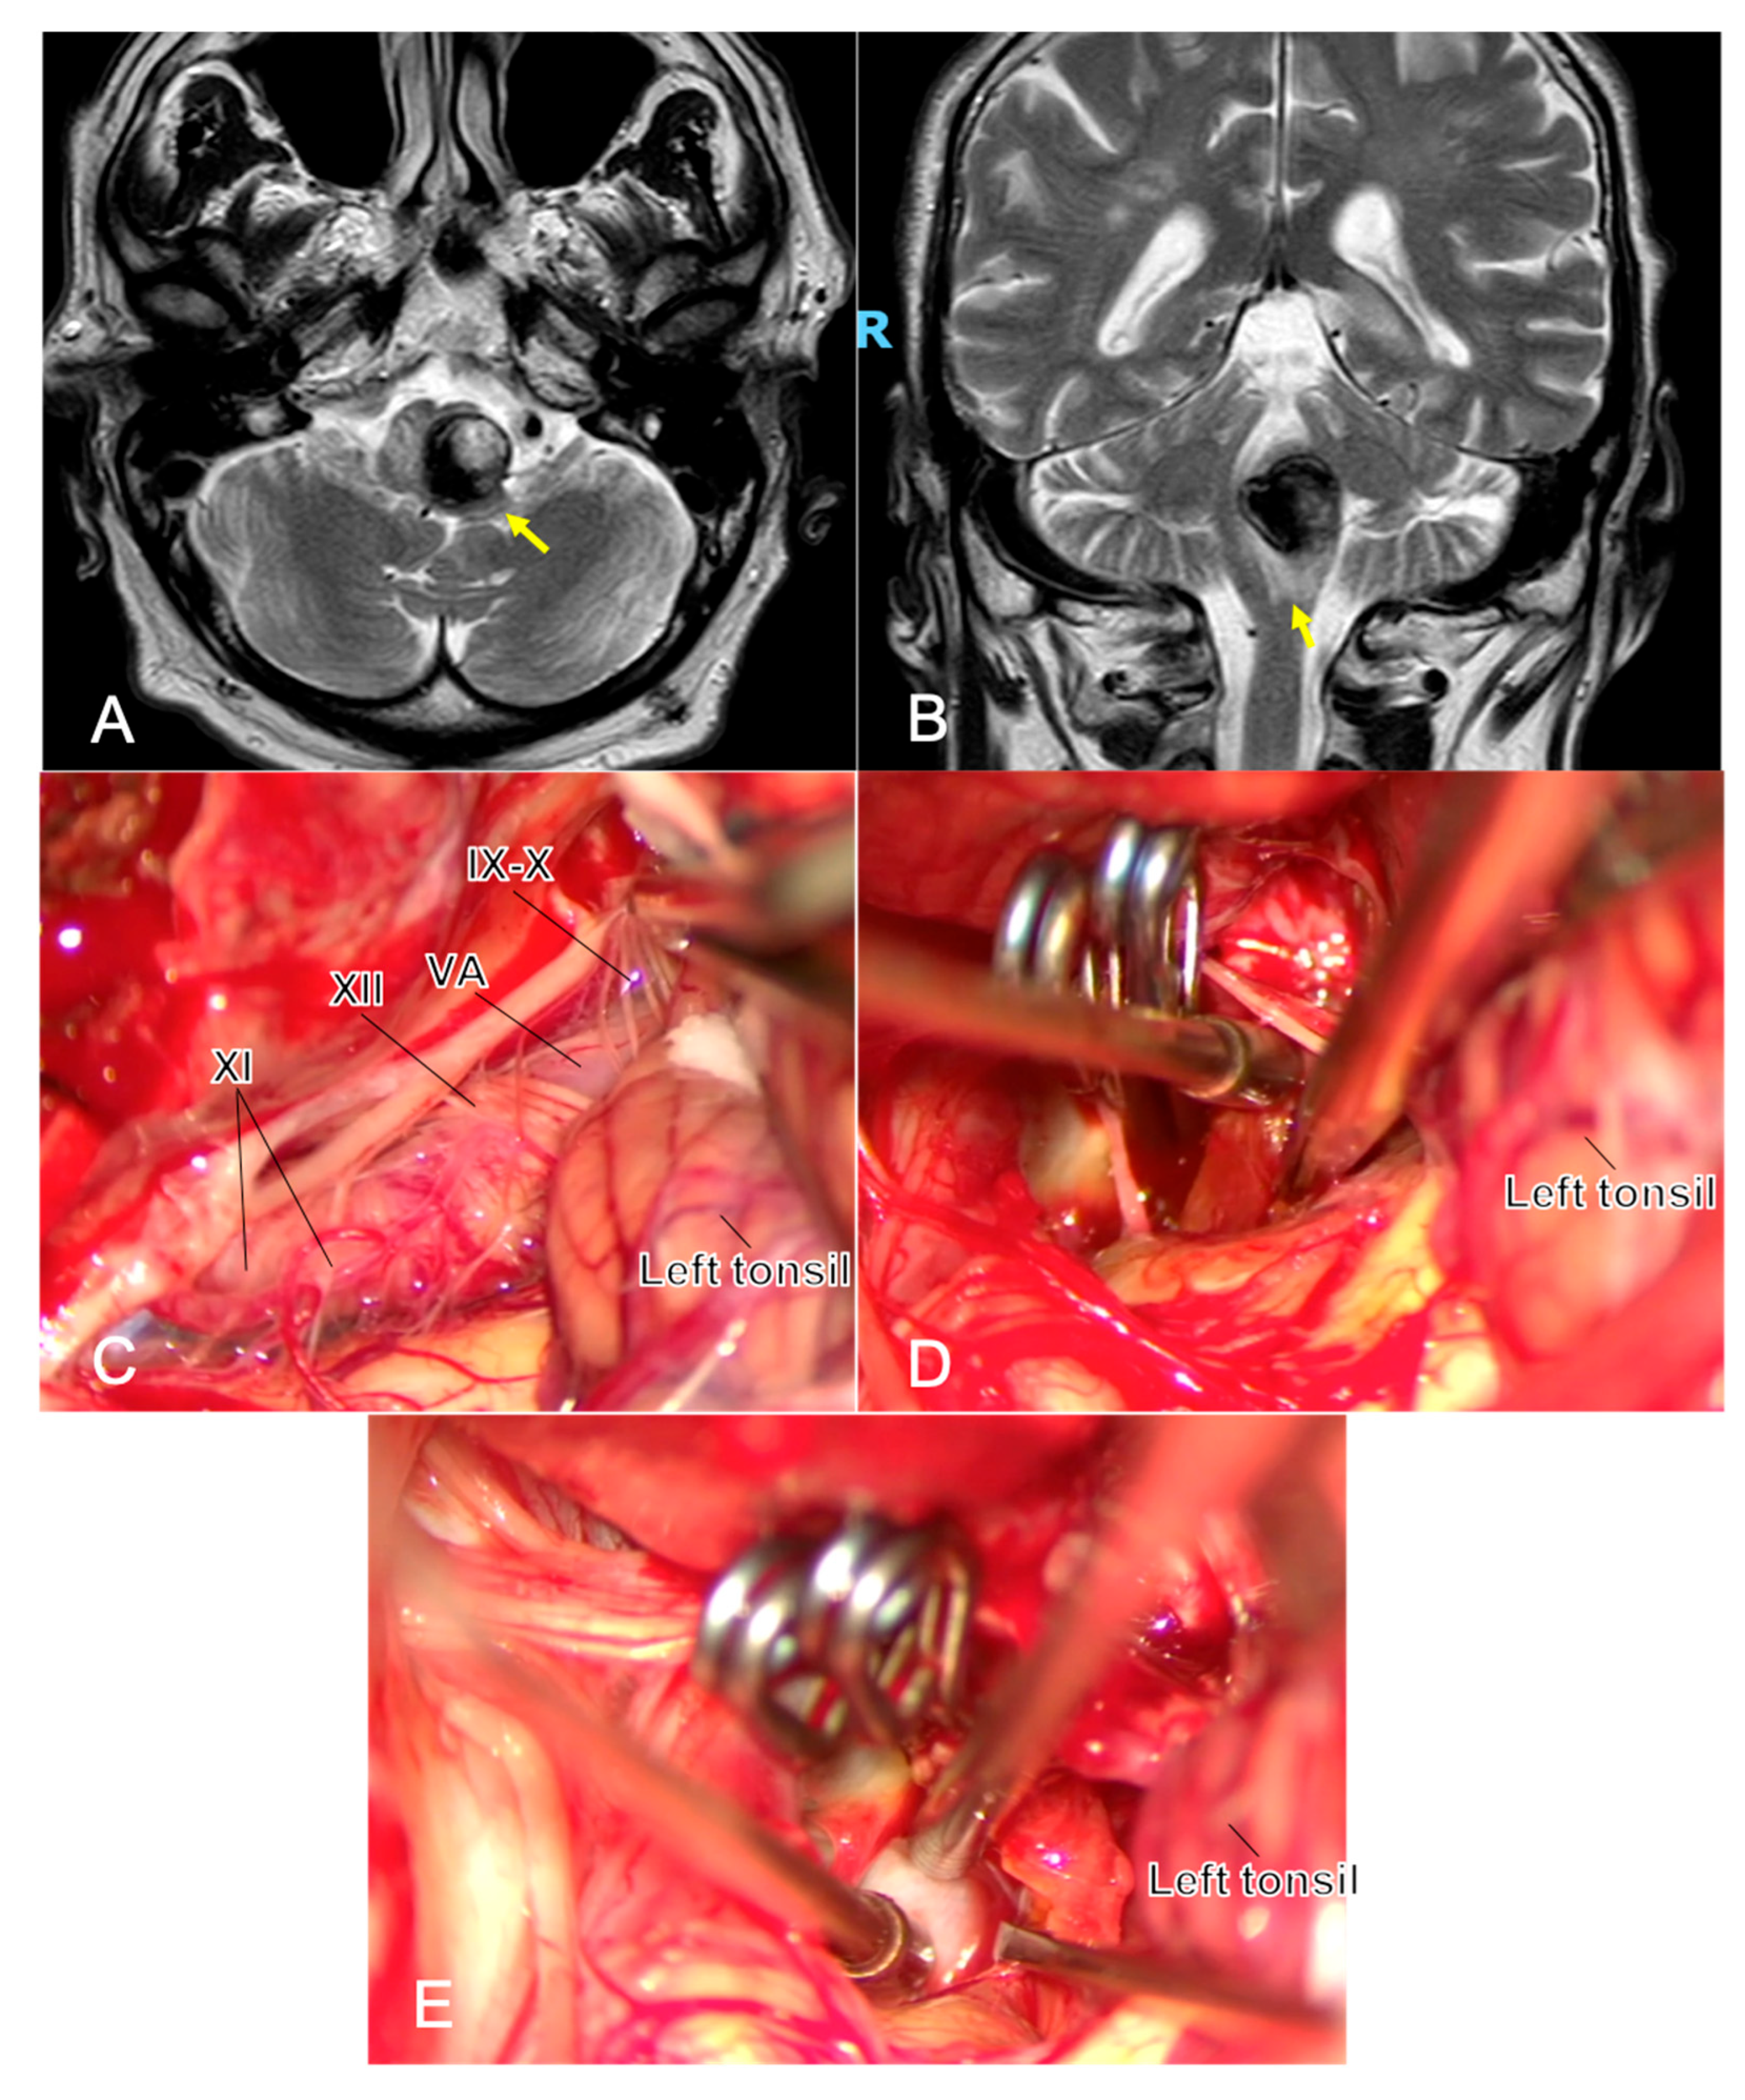

Figure 3. One year after the simple coiling of a previously ruptured p1 PICA aneurysm, a young man developed dysphagia and early right hemiparesis. MRI shows a partially thrombosed recurrent aneurysm at the left VA–PICA junction with marked brainstem compression and surrounding edema ((A,B), yellow arrows). Microsurgical exposure (C) highlights the challenging anatomy at the VA–PICA origin, with the neck arising in close relationship to the lower cranial nerves (IX, X, XI, and XII cranial nerves) and P1 perforators, underscoring the technical difficulty of clip reconstruction in this region. Complete exclusion of the sac is achieved, and the intrasaccular thrombus is evacuated to reduce mass effect (D). Throughout the procedure, micro-Doppler flowmetry and neuromonitoring represent two fundamental tools during this clipping, and in (E), the application of the micro-Doppler flowmetry is shown to confirm proximal/distal vessel patency and complete aneurysm obliteration. Abbreviations: MRI—magnetic resonance imaging; PICA, postero-inferior cerebellar artery; VA, vertebral artery.

Lower cranial nerves (IX–X, XI, XII): During far-lateral/subtonsillar exposure for proximal PICA lesions, proceed with meticulous subarachnoid dissection; avoid suction traction on rootlets; use cranial nerve EMG mapping/stimulation to identify and preserve function, especially after subarachnoid hemorrhage [44] (Figure 3).